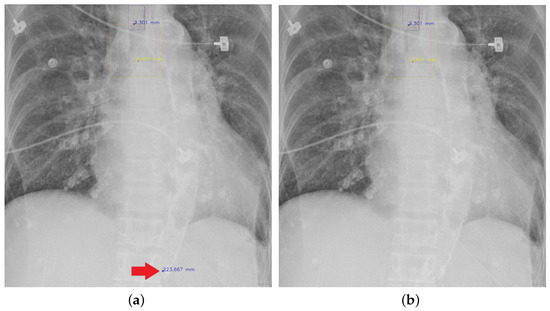

4.5.7. The Post-Process Algorithm

Figure 7 and Figure 8 demonstrate the effect of post-processing. The red bboxes and points in these figures are the GT ETT/bifurcation bboxes and the position of GT ETT tip/Carina, respectively. The green polygon is the GT mask of the ETT and the bifurcation. The blue bbox and point are the predicted ETT bbox and ETT tip, respectively. The yellow bbox and point are the predicted bifurcation and Carina, respectively. Specifically, without the post-process, the model might leave more than one predicted ETT tip/Carina, such as where the red arrow points in Figure 7a. However, with the post-process, the extra points would be removed as shown in Figure 7b. Besides, with the refinement process in the post-process, the feature point of ETT tip/Carina could be further refined as shown in Figure 8. Concretely, the object error of Carina was corrected from 8.469 mm to 1.319 mm.

Figure 7. Ensuring at most one ETT tip/Carina left. (a) Without post-process. (b) With post-process.

Diagnostics 12 01913 g007